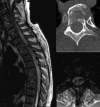

Spinal epidural hematoma (SEH) is a rare cause of nerve root or cord compression; its pathogenesis is not always clearly recognizable. The aim of this paper was to investigate possible etiopathological factors in a consecutive series of patients affected by traumatic SEH treated at our institution. Seven patients with neurologic impairment due to traumatic SEH were retrospectively analyzed after diagnosis and surgical treatment. Thoracic localization was found in 5 cases, and lumbar and cervical localization were found in 1 patient each. One patient was affected by ankylosing spondylitis and one by diffuse idiopathic skeletal hyperostosis. SEH was associated with spine fractures in 6 cases. Only 2 cases of traumatic SEH resulted from high-energy trauma. All patients underwent surgical decompression within 24 hours after admittance to the hospital. Three patients recovered completely, 3 remained paraplegic, and 1 remained monoplegic. Several concomitant conditions are suggested to be predisposing factors for the development of SEH, although its inherent mechanism is still unknown. Two patients in the present series were affected by rheumatologic disorders, confirming the elevated incidence of hematomas in such patients compared to the normal population. Three very unusual cases of SEH occurred in senile patients affected by osteoporotic fractures. Early diagnosis and urgent decompression of the hematoma remain mandatory.